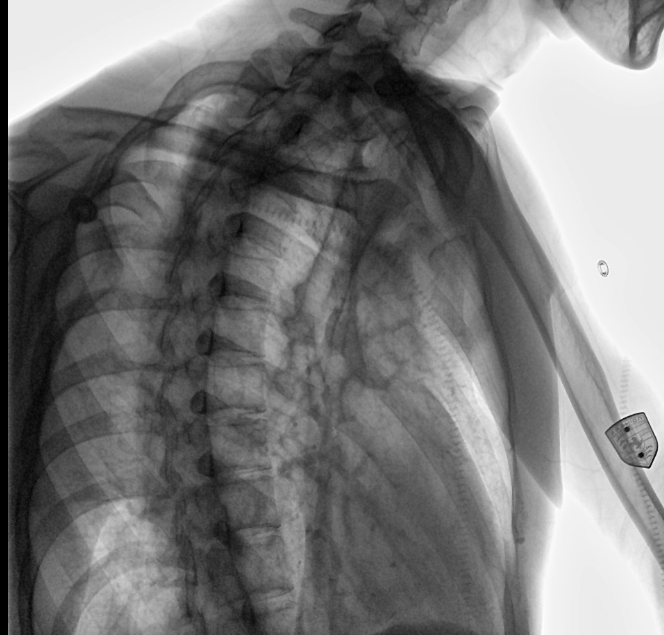

位于衡水市中醫(yī)醫(yī)院的動(dòng)態(tài)平板數(shù)字化X射線系統(tǒng)DTP571具備高速高清點(diǎn)片功能。這是一款對(duì)放射科十分友好的產(chǎn)品。因?yàn)樗迅咚俸透咔妩c(diǎn)片結(jié)合,既能方便影像技師有效地抓拍需要的病灶的影像,又能給予影像醫(yī)生清晰的影像進(jìn)行診斷

動(dòng)態(tài)觀察診斷,實(shí)時(shí)高清點(diǎn)片